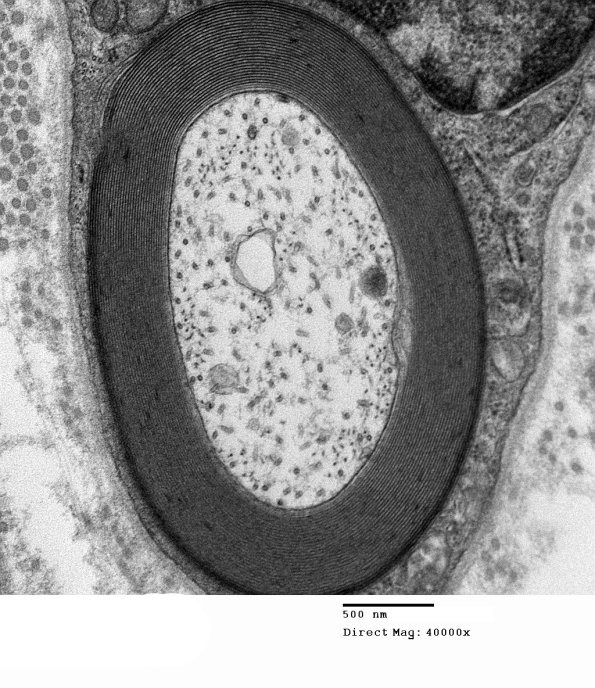

Myelin periodicity is normal from one lamella to another irrespective of its adaxonal (the inner surface of the myelin sheath, closest to the axon) or abaxonal (the outer surface furthest from the axon) location. (electron micrograph)